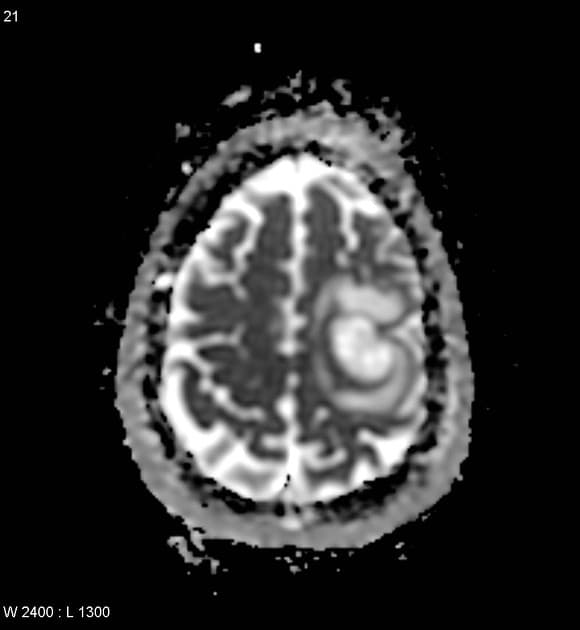

Di căn não từ ung thư phổi kèm di căn lên tuyến tùng

Ung thư phổi đã biết. Thay đổi hành vi kèm lú lẫn.

- Nhiều khối nội trục (intra-axial) ở não, cả vùng trên lều và dưới lều, cho thấy tăng quang (enhancement) dạng đặc, một số có dạng bắt thuốc viền (ring-enhancing) liên quan đến hoại tử trung tâm.

- Khối ở tuyến tùng (pineal gland) có tỷ trọng hơi tăng trên phim không tiêm thuốc cản quang và tăng quang sau khi tiêm thuốc cản quang.

- Quan sát thấy một lớp mỏng xuất huyết trong não thất (intraventricular haemorrhage) ở sừng chẩm của não thất bên phải.

- Khối ở tuyến tùng tăng quang sau khi tiêm thuốc cản quang (mũi tên xanh).

- Lớp mỏng xuất huyết trong não thất (intraventricular haemorrhage) (mũi tên xanh dương) ở sừng chẩm của não thất bên phải.

Di căn não từ ung thư phổi kèm di căn lên tuyến tùng (brain metastases from lung cancer associated with metastasis to the pineal gland)